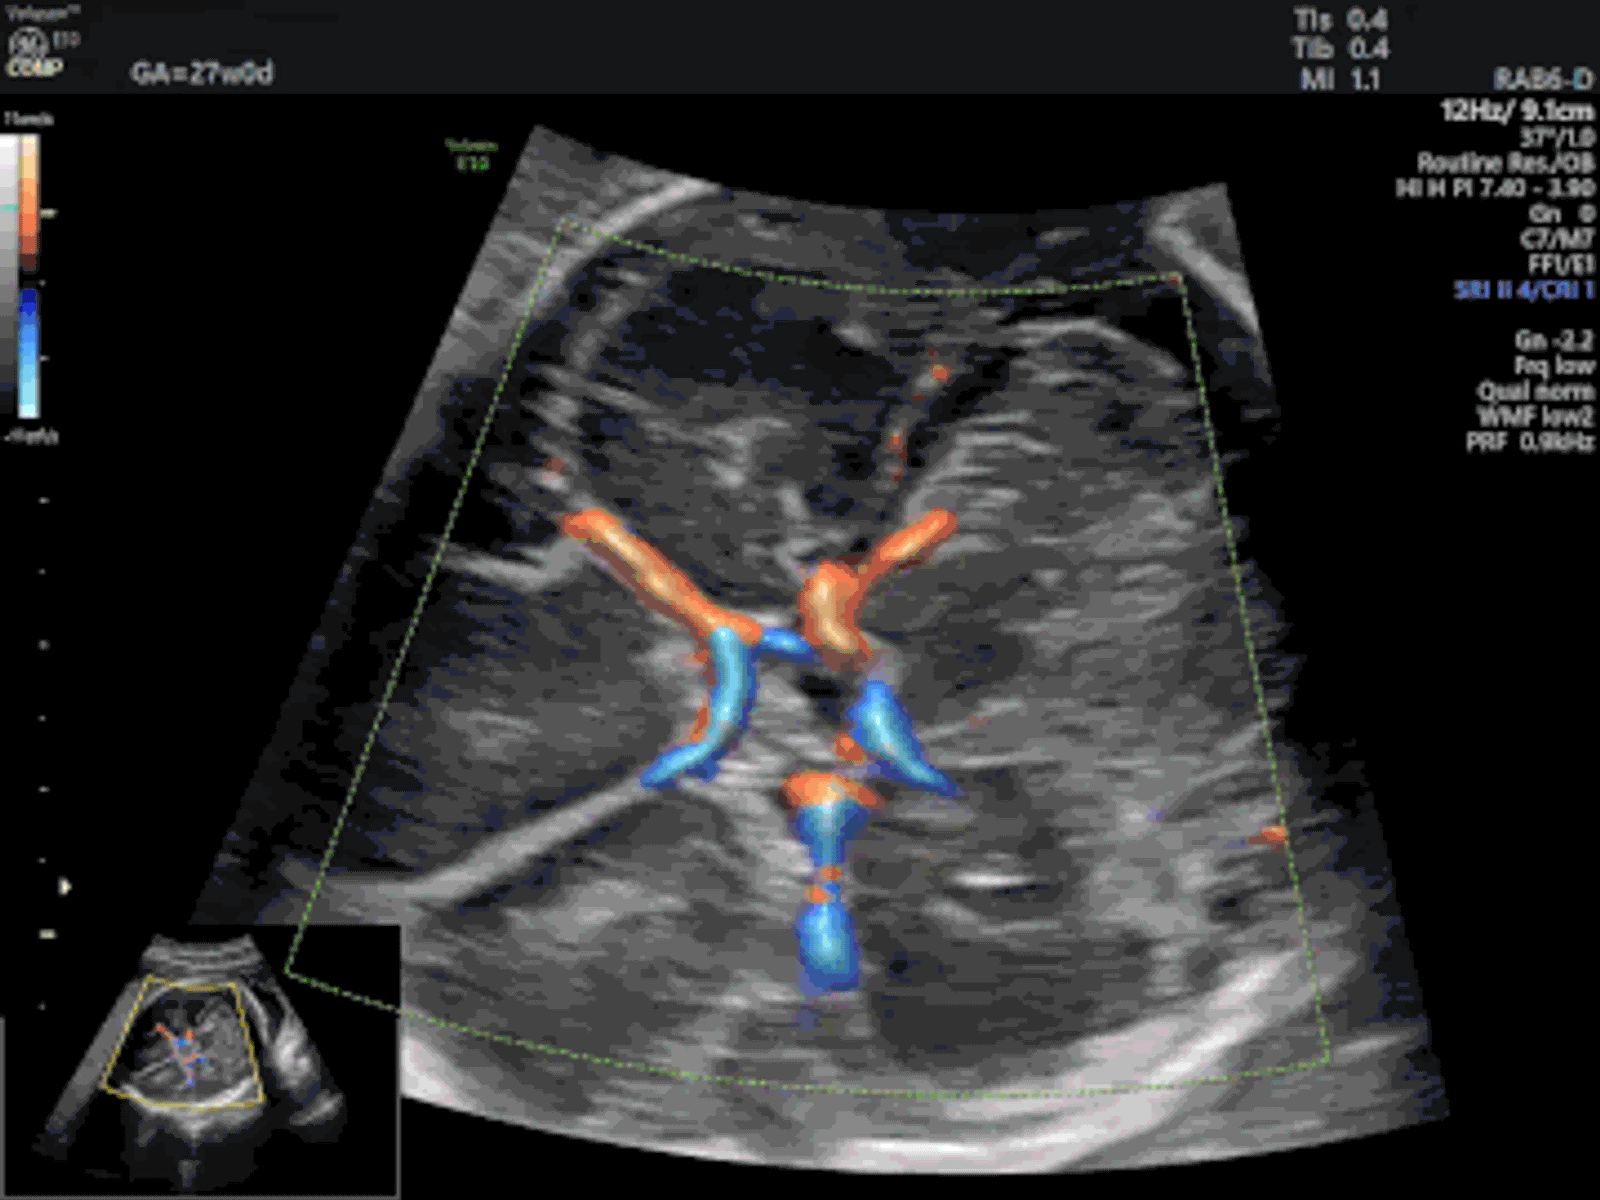

Imaging TechnologyRadiant UltraHD is a GE image rendering technology available on Voluson-series ultrasound systems. It applies real-time post-processing to B-mode images, adjusting brightness, contrast, and sharpness to produce high-definition tissue visualization. The technology improves differentiation between adjacent tissue types, making it easier to identify subtle anatomical boundaries during OB/GYN, abdominal, and vascular exams. Radiant UltraHD is particularly useful in obstetric imaging, where fine tissue detail matters for fetal anatomical assessment and the detection of structural abnormalities.

Radiant UltraHD applies multi-parameter rendering to produce clearer edge definition between adjacent tissue types. This is especially useful in obstetric and gynecological imaging where distinguishing between similar soft tissues affects diagnostic accuracy.

Radiant UltraHD processes raw ultrasound echo data through a multi-parameter rendering pipeline that simultaneously adjusts image brightness, contrast ratio, and edge sharpness. Unlike basic gain adjustments, which affect the entire image uniformly, Radiant UltraHD applies region-aware processing that preserves detail in both near-field and far-field zones. The result is improved visualization of soft tissue boundaries, organ surfaces, and small anatomical structures without the noise amplification that accompanies manual gain increases. On Voluson systems, Radiant UltraHD works alongside HDlive rendering for 3D/4D applications, but its primary strength is in 2D B-mode, where tissue differentiation drives diagnostic confidence. Clinicians scanning dense or heterogeneous tissue benefit most, as the technology pulls out structural detail that might otherwise require additional probe repositioning or post-exam review. The processing happens in real time during live scanning, so there is no workflow delay or separate post-processing step required.